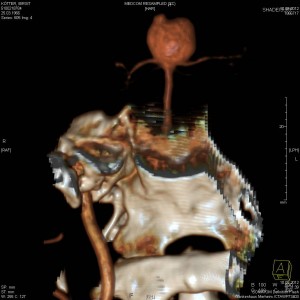

Das ist das Aneurysma: